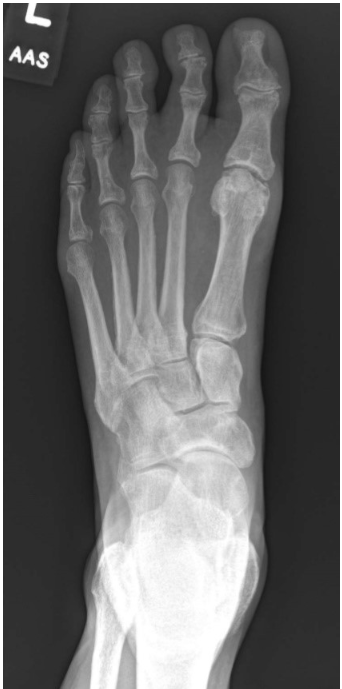

As seen in the following image, the base of the 3rd metatarsals articulates with:

B - 1 and 2 only

The centering point for the AP (dorsoplantar) projection of the foot is at the base of the 3rd metatarsal. This projection should adequately demonstrate the phalanges, metatarsals, and the articulations between the metatarsals and cuneiforms, navicular, and cuboid tarsals. The base of the 3rd metatarsal articulates with the bases of the 2nd and 4th metatarsals, and the lateral (3rd) cuneiform. The medial/first cuneiform articulates with the base of the first metatarsal and navicular. The base of the fifth metatarsal articulates with the cuboid and base of the 4th metatarsal.